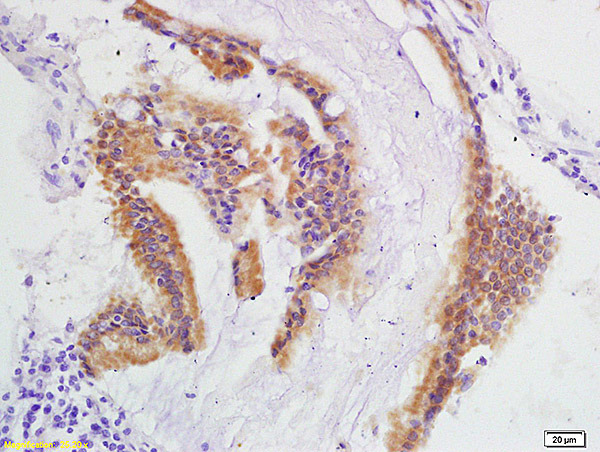

- Main image

- Experimental details

- Formalin-fixed and paraffin embedded human colon carcinoma labeled with Anti-IEX1/Differentiation Dependent Gene 2 protein Polyclonal Antibody, Unconjugated (bs-6840R) at 1:200 followed by conjugation to the secondary antibody and DAB staining

- Sample type

- Human

- Other comments

- Colon